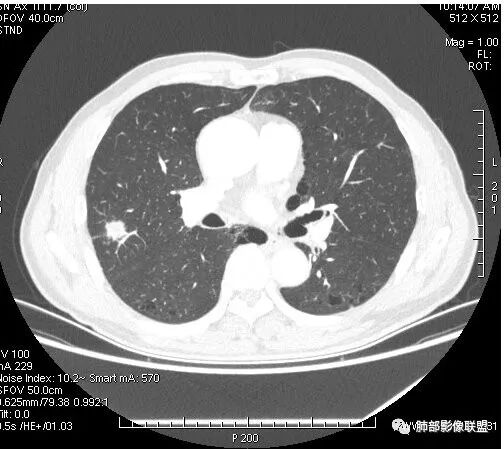

患者右上肺占位,内部强化不均,有空泡,有血管穿过,血管聚集现象,似有胸膜牵拉,考虑恶性

右肺上叶后段占位病灶,病灶不规则,周围胸膜线性牵拉,病灶部分周围有晕,病灶内见不规则空洞,未见明显引流支气管,长毛刺,多分叶、肿块边缘部分L型,可见血管直接供养。增强见点状坏死、病灶内血管。综上考虑恶性可能性大,鉴别隐球菌。

右肺上叶结节,浅分叶膨隆,边缘可见胸膜牵拉及血管集束,不规则厚壁空洞,不均匀强化,血管进入病灶,边缘毛燥,考虑低分化腺癌,鉴别隐球菌。

晨读,右肺上叶结节,边缘膨隆、分叶,部分边缘有平直,可见多发毛刺及胸膜牵拉,牵拉线清秀,收缩力弱,内密度不均,可见片状低密度影及空洞,增强后不均匀强化,血管集束,考虑良性,肉芽肿性结节,鉴别腺癌

晨读:双肺胸膜下多发小气囊,大小不一,右肺结节,内部可见小空洞,洞壁光滑,厚薄不一,偏心性生长,近段血管束增粗,有分叶,毛刺(软),有晕征,平扫密度尚可,增强后不均匀强化,可见低密度坏死,及部分血管穿行,体检发现,考虑恶性:腺癌,鉴别炎性结节

右上叶结节,轻分叶,结节有长短不一毛刺,结节周围GGO边界清,有血管集束征,肺窗结节周围似可见卫星灶,可见鬼脸征,良恶性征象都有,但GGO边界清,浸润性腺癌耍考虑,临床症状轻微,体捡发现,似可见卫星灶和鬼脸征,炎性肉芽肿TB或隐球菌要鉴别。